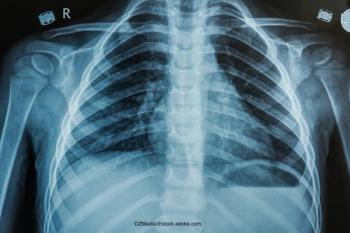

How to correctly diagnose and treat community-acquired pneumoniaByJane M. Carnazzo, MDOctober 7th 2021The winter season of respiratory diseases is nearly here. Knowing how to manage community-acquired pneumonia is essential.

New guidelines for community-acquired pneumoniaByJane M. Carnazzo, MDNovember 13th 2020Recommendations on the diagnosis and management of community-acquired pneumonia.